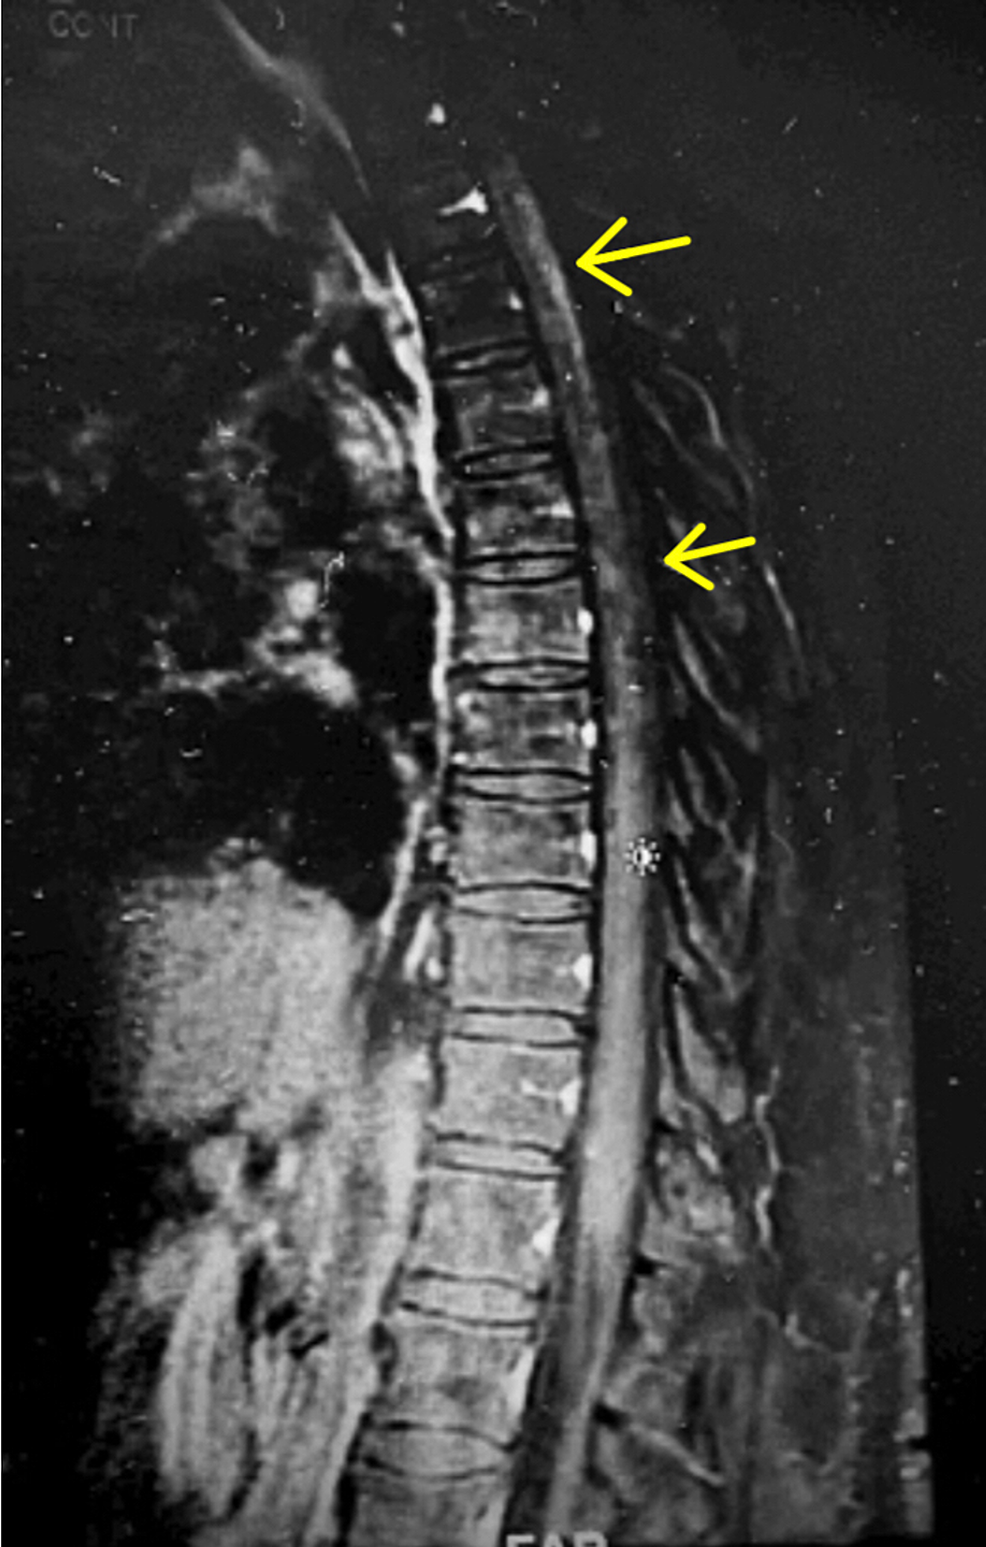

Tabes Dorsalis Mri Findings magnetic resonance imaging (mri) of the dorsal spine showed intramedullary hyperintensity and cord atrophy, similar to. pupillary irregularities, notably the argyll robertson pupil, are characteristic features associated with tabes dorsalis. Presents with symptoms related to dorsal column and dorsal root involvement such as sensory ataxia (tabetic gait), lancinating. late in disease, the most common forms involve the brain and spinal cord parenchyma (general paralysis of the. magnetic resonance imaging (mri) of the dorsal spine showed intramedullary hyperintensity and cord atrophy, similar to. tabes dorsalis is a form of tertiary late neurosyphilis in which there is demyelination of the posterior columns of. Radiologically, there can be spinal cord abnormalities, and also secondary abnormalities, such as charcot joint (neuropathic arthropathy),.

Cureus Tabes Dorsalis in a Patient Presenting With Right Lower Extremity Paresthesia and Tabes Dorsalis Mri Findings tabes dorsalis is a form of tertiary late neurosyphilis in which there is demyelination of the posterior columns of. Presents with symptoms related to dorsal column and dorsal root involvement such as sensory ataxia (tabetic gait), lancinating. magnetic resonance imaging (mri) of the dorsal spine showed intramedullary hyperintensity and cord atrophy, similar to. pupillary irregularities, notably the. Tabes Dorsalis Mri Findings.